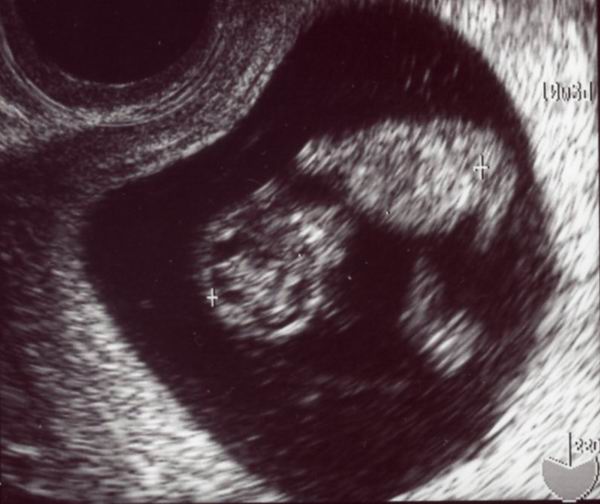

さて,久しぶりのエコー画像。

成長してるでしょう?

左の丸いのが頭,右側が身体,頭からお尻までの長さは

約3cmですって。

ちゃんと人間の形になってるよー!

で,今日も心臓のトクトクがよーく分かりました。

次回は心音聞けるかしら?

赤ちゃんは順調に育っているそうです。